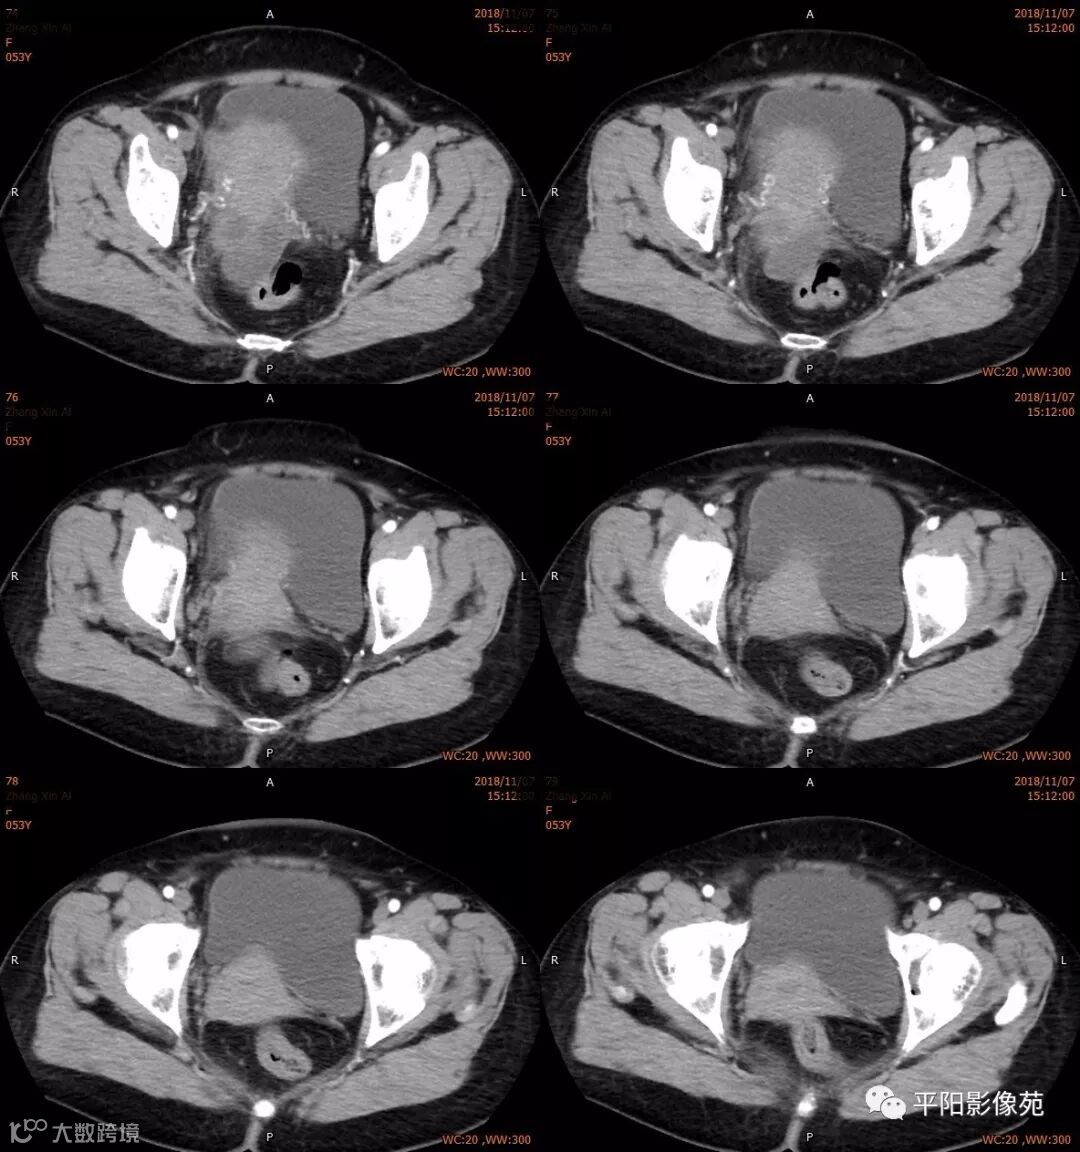

右附件区薄壁囊性病变,壁明显强化,边界不清,供血动脉源自子宫动脉,且局部动脉血管增多;其内侧可见卵圆形无强化囊性病灶。

附件区病变多见于卵巢,以囊性为主的病灶多为卵巢囊肿、粘液/浆液性囊腺瘤、皮样囊肿等,这些病灶都具有鲜明瘤体结构,且壁强化多为轻-中度,供血动脉多源自卵巢动脉;而本例患者右附件区薄壁囊性病灶,多位置观察形态为迂曲管状,且壁有明显延迟强化,供血动脉源自子宫动脉,较对侧血管丰富,故而考虑源自输卵管或子宫病变,但子宫发生的薄壁囊性病变较少,多见于子宫肌瘤囊变,完全囊变者少见,且形态轮廓与肌瘤相同为球形故而排除,结合患者腹痛前有感冒病史,且有压痛,因此考虑输卵管积脓可能。其内侧无强化囊性肿块,考虑卵巢囊肿可能。